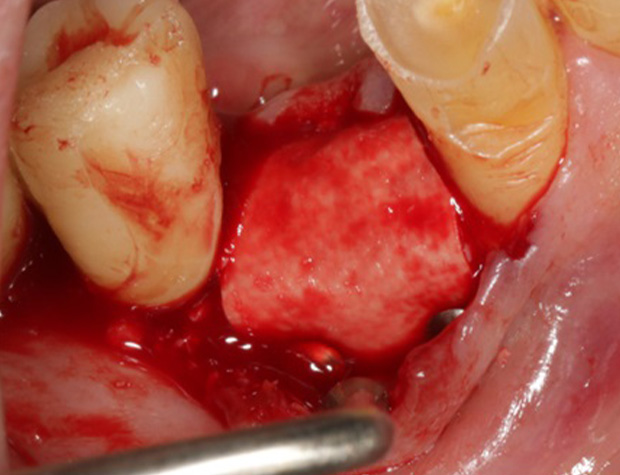

Implantologische Fälle schnell und einfach lösen ist der Wunsch eines jeden Implantologen. Die Realität ist allerdings eine andere. Diverse Knochendefekte, schlechte Knochenqualität, Weichgewebsdefizite und viele weitere schlechte Grundvorraussetzungen existieren und machen jeden Eingriff zu einer Herausforderung. Um solche implantologischen Fälle dennoch erfolgreich zu therapieren, benötigen Sie einfach handhabbare Techniken, die schnell zu erlernen sind und nahezu jeden Fall realisierbarer gestalten kann. Die Osseodensifikation ist eine Technik die schnell und einfach zu erlernen ist und viele Möglichkeiten Ihnen bietet. Das Implantatbett bei schlechter Knochenqualität optimal aufbereiten ist bereits bekannt, aber einen Kieferkamm spreizen oder sogar einen Sinuslift vorhersagbar durchzuführen, ohne die Schneider’sche Membran zu perforieren, das sind die Optionen, die Sie schnell und einfach erlernen können. Um Ihr Portfolio noch zu erweitern, wird die GBR-Technik mittels moderner Materialien Ihnen beigebracht.